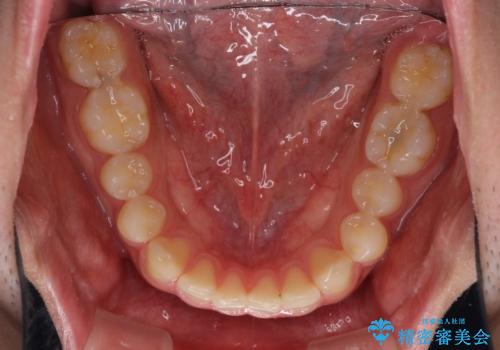

インビザラインによる、すきっ歯の改善

- 前歯がすきっ歯であることを気にして来院された患者様です。

下の前歯がほとんど隠れてしまうくらいの深い咬み合わせであったので、インビザラインを用いて、咬み合わせの高さを改善しながら隙間を閉じていくこととしました。

咬合力で上の前歯が前方に押し出されるようにして隙間ができていましたが、矯正治療により全て閉じることができました。

深い咬み合わせも多少改善され、隙間も閉じたことで、前方に出ていた前歯が引っ込んだため、口も閉じやすくなったとのことでした。